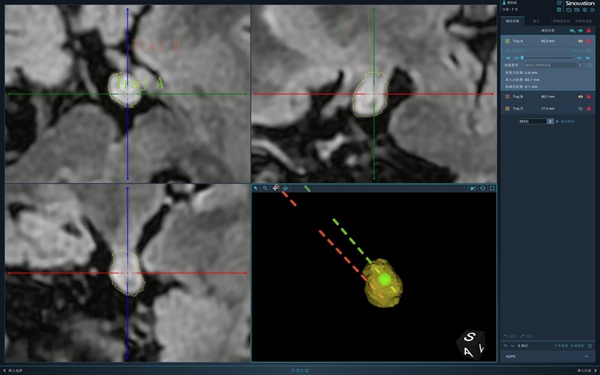

插入腫瘤的2根電極示意圖。重醫附屬兒童醫院供圖

經過充足的術前準備后,翟瑄帶領團隊利用手術機器人精準確定腫瘤位置,在機器人引導下,準確地將兩根立體定向深部電極同時置入到女童顱內腫瘤里,再通過視頻腦電圖監測確定腫瘤內部具體“異常放電”的電極點及強度,利用反向電流加熱電極對腫瘤進行熱凝損毀,最終“摧毀”腫瘤。這樣就能達到消除癲癇發作的作用,待手術成功后再將電極安全取出。